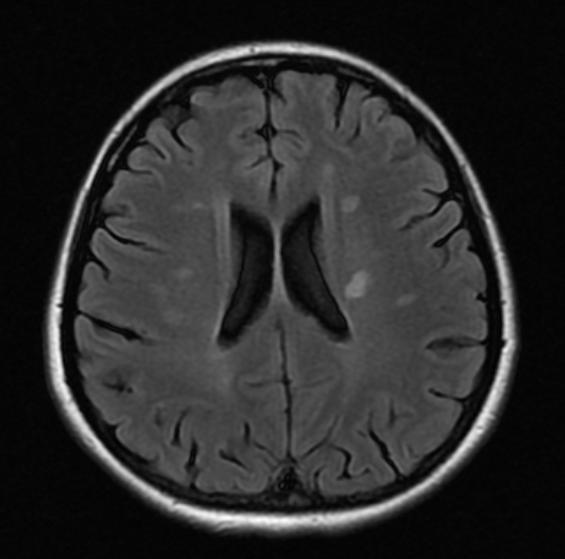

Objetivo: Relatar o caso de recidiva de herpes-zoster (HZ) em paciente com esclerose múltipla (EM) em uso de tratamento imunomodulador (natalizumabe) com evolução favorável. Descrição de caso: Mulher de 39 anos com diagnóstico de EM há 1 ano e 6 meses, previamente tratada com interferon 1a, começou tratamento com natalizumabe, desenvolvendo HZ após três meses de tratamento. HZ foi tratado com aciclovir, por sete dias, via oral. Seguimento ambulatorial após três meses de tratamento mostrou resolução completa das lesões, sem desencadeamento de neuralgia pós-herpética. Conclusões: As novas terapias para a EM podem estar relacionadas a diferentes tipos de efeitos adversos. Nem todos os casos de HZ, associados com novas terapias para EM, evoluem de forma desfavorável. Estudos são necessários para reconhecer os fatores de riscos para as formas graves de HZ em tais pacientes.